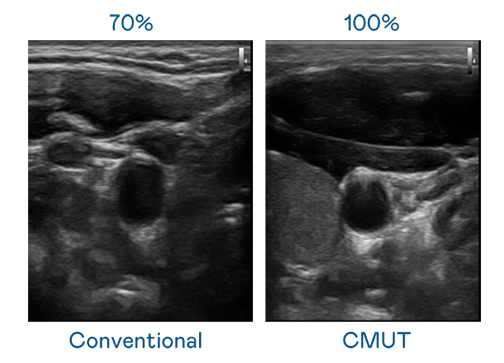

CMUT 技術是一種用電容式微機電元件來產生超音波訊號的技術。與傳統 PZT 壓電式技術相比,CMUT 頻寬增加 30%,更寬頻的超音波訊號讓影像解析度大幅提升,是實現高影像品質醫療超音波掃描、促進精準醫療發展的關鍵技術。

超音波影像的解析度高低,首先取決於探頭能發出的訊號頻寬。二区aa级无人二区 CMUT 可提供高清晰的超音波訊號,提供高頻寬、高靈敏度、影像紋理細節更高的超音波影像,協助醫護人員縮短影像判讀時間及利用精準的醫療影像進行診斷。